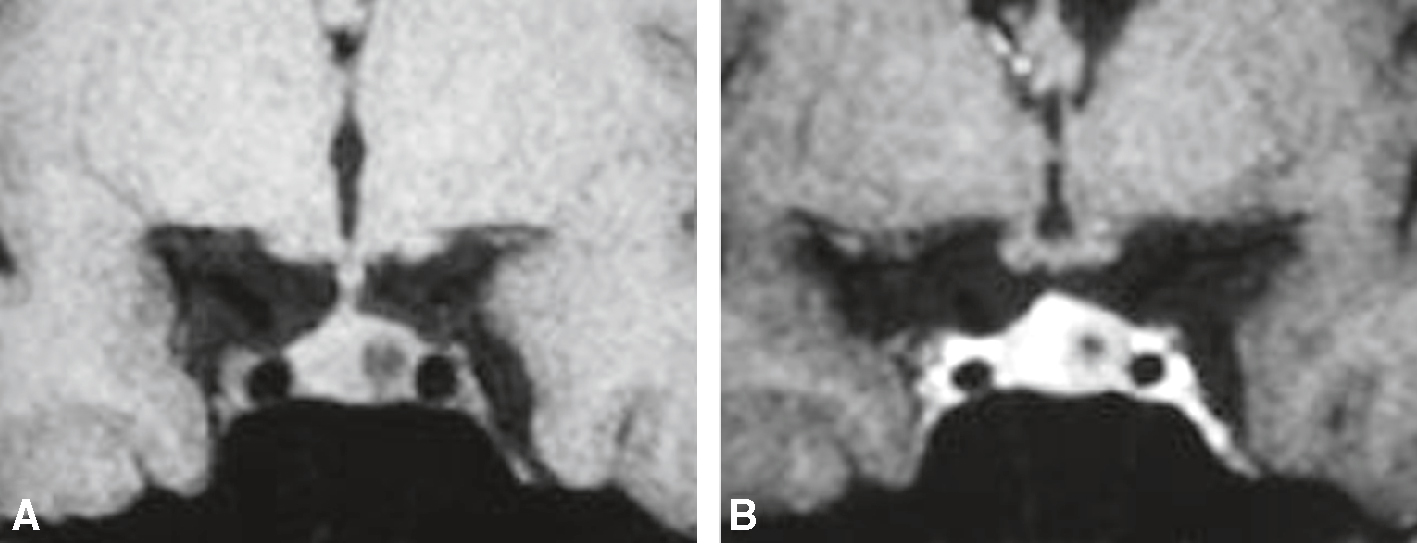

IRM, séquence T1 dans le plan coronal, avant et après injection de gadolinium chez une femme de 45 ans réalisée dans le cadre d’un bilan d’hyperprolactinémie. Signes directs : lésion intrasellaire focale arrondie, infracentimétrique, développée dans l’aileron hypophysaire gauche, en hyposignal avant injection et restant en hyposignal après injection (rehaussement beaucoup moins rapide que l’hypophyse normale). Signes indirects : surélévation modérée du diaphragme sellaire à gauche et déviation controlatérale de la tige pituitaire. A. T1 frontal sans injection. B. T1 frontal après injection.

Deux trophées IRM coronaux dans la séquence T1 montrent la zone de la glande hypophysaire d'un patient de 45 ans examiné pour l'hyperprolactinémie. Avant d'injecter du gadolinium, cette photographie mettait en vedette la glande hypophysaire généralement iso-centrique avec une apparence asymétrique séparée de la boucle avant. L'image B recevant l'injection après l'injection met en évidence le contraste hétérogène dans la glande pituitaire avec des zones de réadaptation du lobe bas de l'hypophyse, indiquant la présence de la glande pituitaire microadénomes. Cette amélioration différentielle permet une meilleure distinction des lésions du parenchyme hypophysaire normal. Cela conduit au diagnostic de l'adénome de la prolactine, une cause commune d'hyperprolactinémie pendant les services de garde.